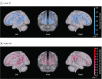

Main outcomes and measures: ScreenQ is a 15-item measure of screen-based media use reflecting the domains in the AAP recommendations: access to screens, frequency of use, content viewed, and coviewing. Higher scores reflect greater use. ScreenQ scores were applied as the independent variable in 3 multiple linear regression models, with scores in 3 standardized assessments as the dependent variable, controlling for child age and household income: Comprehensive Test of Phonological Processing, Second Edition (CTOPP-2; Rapid Object Naming subtest); Expressive Vocabulary Test, Second Edition (EVT-2; expressive language); and Get Ready to Read! (GRTR; emergent literacy skills). The DTI measures included fractional anisotropy (FA) and radial diffusivity (RD), which estimated microstructural organization and myelination of white matter tracts. ScreenQ was applied as a factor associated with FA and RD in whole-brain regression analyses, which were then narrowed to 3 left-sided tracts supporting language and emergent literacy abilities.

Results: Of the 69 children recruited, 47 (among whom 27 [57%] were girls, and the mean [SD] age was 54.3 [7.5] months) completed DTI. Mean (SD; range) ScreenQ score was 8.6 (4.8; 1-19) points. Mean (SD; range) CTOPP-2 score was 9.4 (3.3; 2-15) points, EVT-2 score was 113.1 (16.6; 88-144) points, and GRTR score was 19.0 (5.9; 5-25) points. ScreenQ scores were negatively correlated with EVT-2 (F2,43 = 5.14; R2 = 0.19; P < .01), CTOPP-2 (F2,35 = 6.64; R2 = 0.28; P < .01), and GRTR (F2,44 = 17.08; R2 = 0.44; P < .01) scores, controlling for child age. Higher ScreenQ scores were correlated with lower FA and higher RD in tracts involved with language, executive function, and emergent literacy abilities (P < .05, familywise error-corrected), controlling for child age and household income.

Conclusions and relevance: This study found an association between increased screen-based media use, compared with the AAP guidelines, and lower microstructural integrity of brain white matter tracts supporting language and emergent literacy skills in prekindergarten children. The findings suggest further study is needed, particularly during the rapid early stages of brain development.